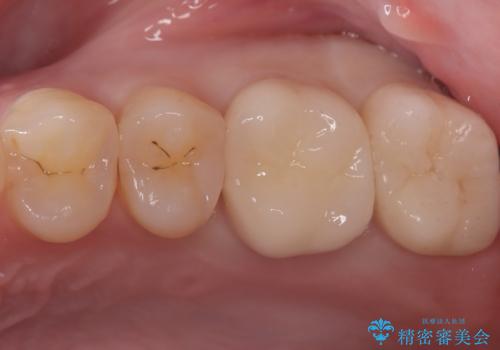

欠けやすい大きなプラスチック充填から、耐久性の高いセラミッククラウンへ

担当医 河口智英